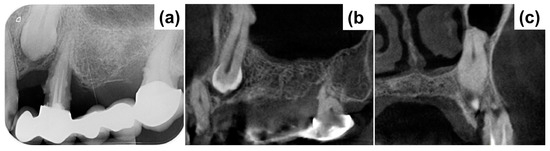

The planned extraction of the impacted teeth 23 and 24 would leave a complex and deep bone defect, with horizontal and vertical components. Therefore, the first surgical step was dedicated to the removal of 23 and 24 and subsequent defect management. The resulting bone defect was considered complex given the deep vestibular bone loss at location 23 and the vertical component of the defect between areas 23 and 24 (Figure 2b).

Heterologous bone (cerabone®, botiss biomaterials GmbH, Zossen, Germany) in a granular form was used as the bone substitute to augment the defect (Figure 2c). The sintered bovine bone provides excellent volume stability with only superficial degradation [29]. It also has a reported excellent hydrophilicity [30], which promotes the infiltration of blood and precursor cells for promoting vascularization [31,32] and osseous integration [33].

Due to the presence of a vertical component, a rigid magnesium membrane (NOVAMag® membrane, botiss biomaterials GmbH, Zossen, Germany) was necessary to obtain a stable volume, able to resist the pressure of the overlying soft tissue when closing the flap. This membrane, despite having a typically metallic appearance and rigidity, has the ability to be completely reabsorbed in approximately 4 months. This device was bent, cut, and refined, and then adapted to create an arch over the defect (Figure 2d). The membrane was secured to both the buccal and palatal walls using titanium pins (Titan-Pins, Ustomed, Tuttlingen, Germany). The magnesium membrane was covered with a resorbable membrane made of porcine pericardium (Jason®, botiss biomaterials GmbH, Zossen, Germany) in order to allow an easier adaptation of the overlying flap (Figure 2e). The collagen membrane was also stabilized using the metal pins. The first intention closure completed the first surgical phase (Figure 2f). No removable temporary was applied so as not to interfere with the healing phase.

During the follow-up period, there were no complications and the soft tissue healed well, leaving a thick keratinized tissue above the treated site (Figure 2g). A periapical X-ray was taken after 8 months to assess the stability of the grafted material and bone (Figure 3a). The X-ray confirmed good maintenance of the augmented bone volume. Upon reentry, a muco-periosteal flap was elevated and successful bone regeneration was proven (Figure 3b). Two implants were placed at the sites 23 and 26 (BLT, Straumann, Switzerland), and healing abutments were placed immediately for non-submerged healing (Figure 3c,d).

Figure 2. Augmentation of the bony defect. (a) Initial clinical situation, (b) bone defect after the extraction on 23 and 24, presenting a vertical and horizontal component, (c) application of the bovine bone graft, (d) placement of the magnesium membrane, cut into a rounded strip and bent over the defect to provide a supporting arch, (e) positioning of a pericardium membrane, (f) first intention closure, (g) healed site at 8 months.